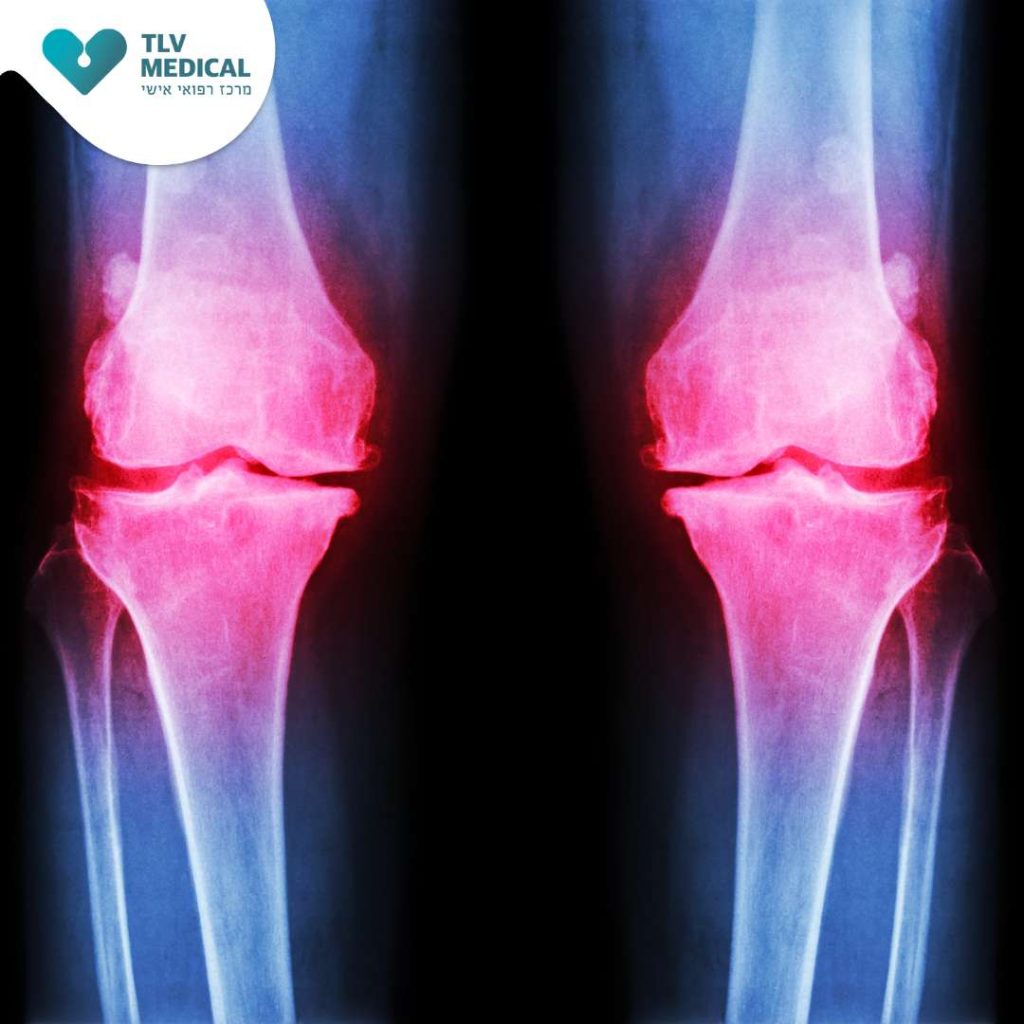

אבחון דלקת מפרקים ניוונית נעשה על זיהוי התסמינים הקליניים, בדיקה גופנית ושימוש בהדמיה (דימות). בצילומי רנטגן ניתן לראות היצרות באזור המפרק, לעיתים היווצרות בליטה גרמית על העצם (אוסטאופיטים).